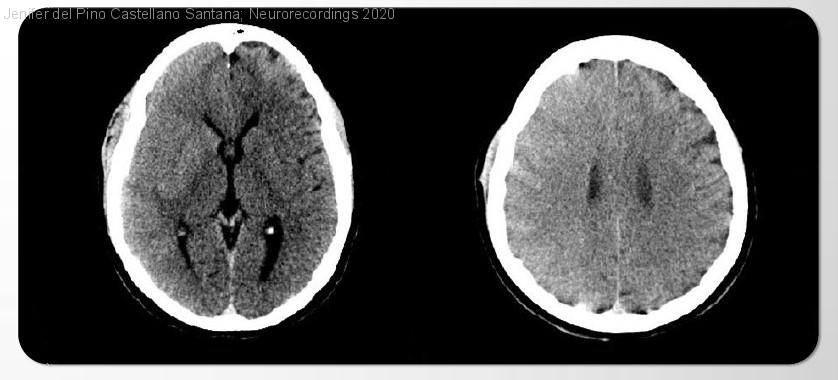

Encefalopatía inducida por contraste tras procedimiento endovascular

Diagnóstico final: Encefalopatía inducida por contraste

Mujer de 44 años sin antecedentes de interés que desde hace 3 semanas presenta cefalea intensa hemicraneal derecha con edema periocular ipsilateral y visión doble. En la exploración neurológica destaca quemosis y proptosis ocular derecha con limitación para abducción,...